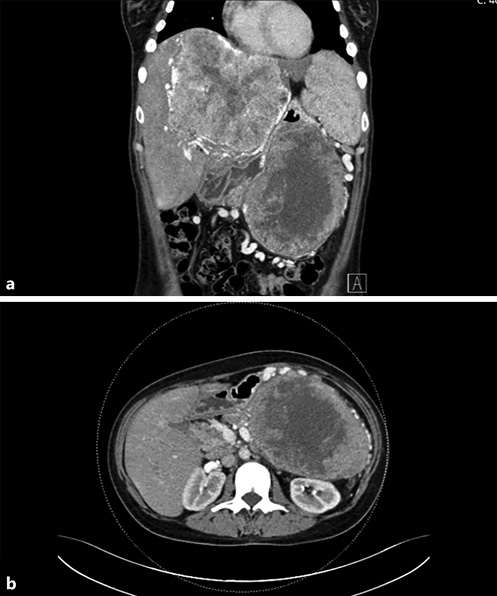

Computed tomography (CT) is the gold standard for the detection and evaluation of pancreatic masses, being the most frequently performed imaging modality in patients with SPNs [5, 14]. This neoplasm will appear on CT as a completely or incompletely encapsulated mass, unusually nonencapsulated, with both solid and cystic areas (shown in Fig. 1). Solid areas, sometimes appearing in the form of calcifications, are typically peripherical and correspond to pseudopapillary areas, whereas cystic areas are characteristically central and correspond to hemorrhagic degeneration. Contrast-enhanced CT (CECT) shows generalized weaker early arterial enhancement, but stronger portal-venous phase enhancement in the solid component [26, 29].

Fig. 1 Contrast-enhanced coronal (a) and axial (b) CT showing a large mass in the tail of the pancreas, with central hypodensity and heterogenous peripherical enhancement, associated with a giant hypervascular hepatic mass (a).